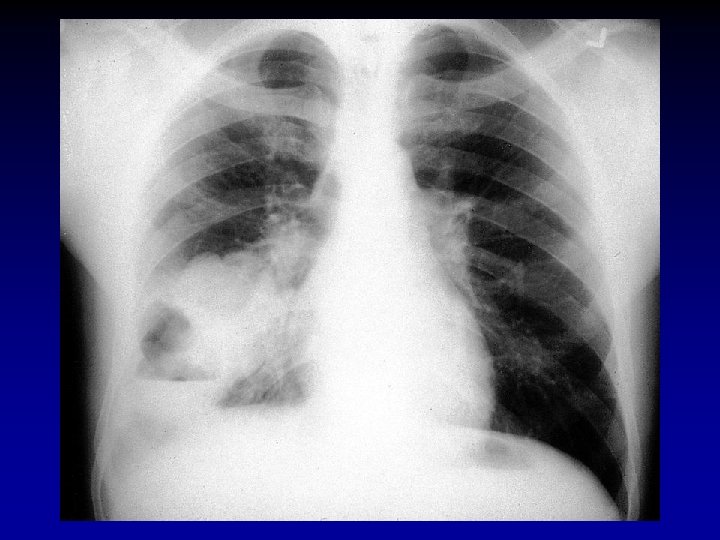

Akciğer Grafisi • Posteroanterior grafi Pnömoninin • Yerini • Komplikasyonlarını • Pnömoniyi taklit eden durumları saptar.

Akciğer Filmi • Pnömoni düşünülen her hastada PA akciğer filmi çekilmelidir • Radyolojik görünümle etyolojik tanıya varmak mümkün değildir • Antibiyotik tedavisine yanıt alınıyorsa bir kontrol filmi yeterlidir • Bazı pnömonili olgularda akciğer filmi normal görünümde olabilir (Pnömoninin ilk 24 saatinde, dehidratasyon, yaşlı, pnömosistis karini, ciddi nötropenik hastalarda)

Akciğer Grafisi • Pnömokok, Klebsiella • Lober tutulum • S. aureus, P. aeruginosa • Bronkopnömonik görünüm • S. aureus • Legionella • Pnömatosel, yeri değişen nodüler infiltrasyonlar, apse • Zaman içinde değişebilir veya baştan itibaren lober

TKP Ağırlık Faktörleri • • • Fizik muayene Şuur değişikliği Ateş <35 C ya da->40 C Kan basıncı<90 mm. Hg Solunum sayısı>30/dak Siyanoz • • Laboratuvar BK< 4000 mm 3, >30. 000 mm 3 Nötrofil < 1000/mm 3 Pa. O 2<60 mm. Hg Sa. O 2<%92, p. H<7. 35 BUN>30 mg/dl Na<130 m. Eq/L Akciğer filminde multilober tutulum, kavite, plevral effüzyon, hızlı ilerleme • Sepsis ya da MODS

TKP Yoğun Bakıma Yatırılma Kriterleri • • • Mekanik ventilasyon ihtiyacı Septik şok tablosu Konfüzyon Kan basıncı < 90 mm/Hg Solunum sayısı > 30/dak, idrar miktarı < 20 ml/saat • Akut böbrek yetmezliği • Akciğer filminde multilober tutulum, 48 saate opasitede %50’den fazla artış